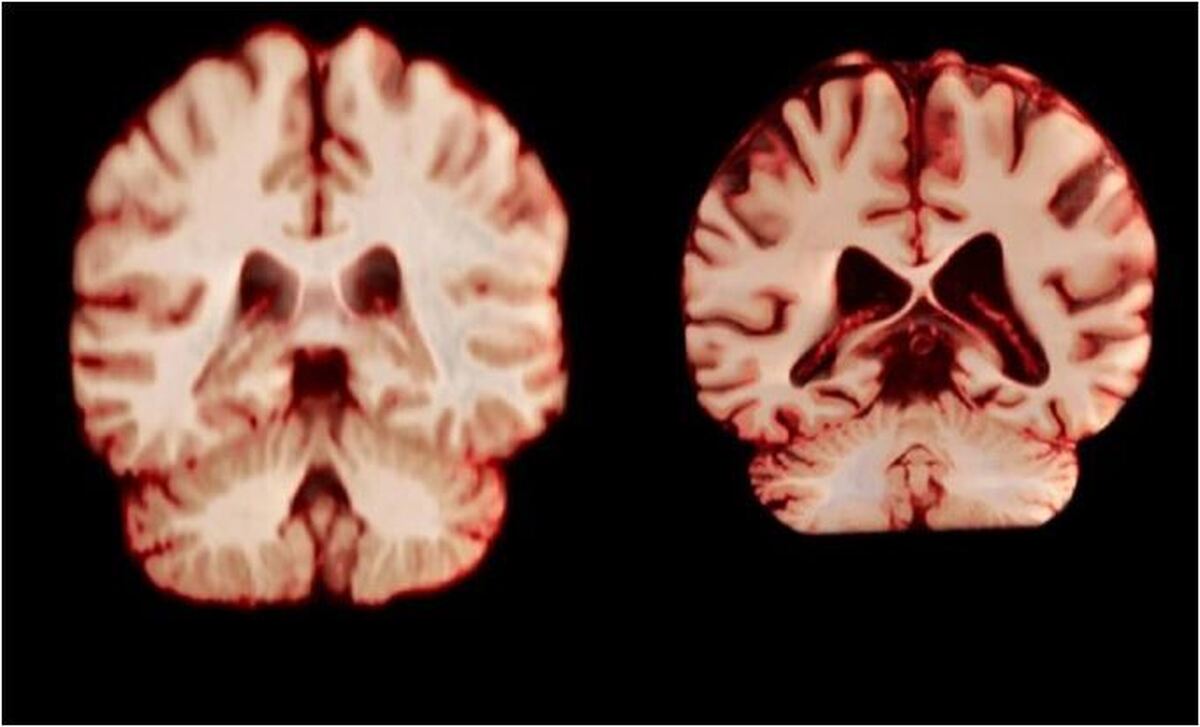

مغز زنان کُندتر پیر می‌شود، اما به نظر نمی‌رسد که این موضوع آنها را از ابتلا به نوع شایع زوال عقل محافظت کند.

به گزارش مجله خبری نگار، بر اساس یک مطالعه طولی که امروز در مجموعه مقالات آکادمی ملی علوم منتشر شد، در طول پیری، مردان در مقایسه با زنان، کاهش حجم بیشتری را در مناطق بیشتری از مغز تجربه می‌کنند. نویسندگان معتقدند این بدان معناست که تغییرات مغزی مرتبط با سن توضیح نمی‌دهد که چرا زنان بیشتر از مردان به بیماری آلزایمر مبتلا می‌شوند.

زنان تقریبا دو برابر مردان به بیماری آلزایمر مبتلا می‌شوند و پیری بزرگترین عامل خطر برای این بیماری است. این موضوع باعث شده است که تحقیقاتی در مورد تفاوت‌های جنسیتی مرتبط با سن در مغز انجام شود. آن راوندال، دانشجوی دکترا در دانشگاه اسلو و یکی از نویسندگان این مقاله، می‌گوید: اگر مغز زنان بیشتر تحلیل رفته باشد، این می‌تواند به توضیح شیوع بالاتر آلزایمر در آنها کمک کند.

جدیدترین مطالعه شامل بیش از ۱۲ هزار و ۵۰۰ اسکن مغزی تصویربرداری تشدید مغناطیسی (MRI) از ۴۷۲۶ نفر بود که حداقل دو اسکن برای هر نفر، با فاصله متوسط سه سال انجام شده بود که به بیماری آلزایمر یا هرگونه اختلال شناختی مبتلا نبودند و به عنوان شرکت‌کننده کنترل در ۱۴ مجموعه داده بزرگتر قرار داشتند. محققان با بررسی عواملی از جمله ضخامت ماده خاکستری و اندازه نواحی مرتبط با بیماری آلزایمر، مانند هیپوکامپ که برای حافظه ضروری است، نحوه تغییر ساختار مغز افراد را در طول زمان مقایسه کردند.

به طور کلی، مردان در مقایسه با زنان، کاهش حجم بیشتری را در مناطق بیشتری از مغز تجربه کردند. به عنوان مثال، قشر پس مرکزی که مسئول پردازش احساسات لامسه، درد و دما و همچنین موقعیت و حرکات بدن است، در مردان سالانه ۲.۰ درصد و در زنان سالانه ۱.۲ درصد کاهش یافت.